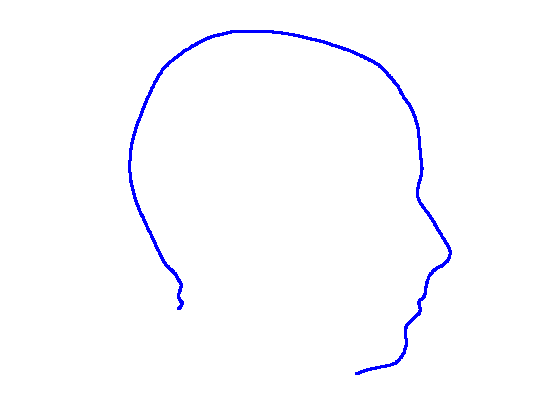

5.8 Ellipse fitting

Ellipse fitting was motivated by the fact that large sections of the cranium appeared to be elliptical in form, thus suggesting a natural centre and frame origin with which to model cranial shape. An ellipse belongs to the set of curves known as conics, which can be defined by the equation:

| (4) |

and if is constrained such that the discriminant is negative, then the conic is an ellipse. We use the nasion landmark position to segment out the cranium region from the face and use a robust iterative ellipse fitting procedure that rejects outliers. The core of this algorithm is the Direct Least Squares Fitting of Ellipses approach of Fitzgibbon et al [30], which presents a solution for as the solution of an eigensystem that enforces the required constraint on the discriminant.

However, the algorithm in its raw form is insufficient as we need to reject outliers, as is often caused by the latex cap peak worn by imaged subjects. Thus we use an iterative call to the procedure in [30] that rejects outliers outside some threshold of the fitted ellipse contour, iterating until the inlier set becomes stable or a maximum number of iterations is reached.

Figure 16 shows examples of the robust ellipse fit for four head profiles. The centre of the ellipse is used in a pose normalisation procedure where the ellipse centre is used as the origin of the profile and the angle from the ellipse centre to the nasion is fixed at -10 degrees. We call this Ellipse Centre - Nasion (ECN) pose normalisation and later compare this to GPA. The major and minor axes of the extracted ellipses are plotted as red and green lines respectively in Fig. 16.

|

|

|

|

Figure 17 shows all 100 profiles overlaid with the same alignment scheme. The median value of major ellipse axis and the ellipse centre-nasion angle differ by 3.6 degrees, so that when the nasion angle is fixed at -10 degrees, the median ellipse angle is -6.4 degrees (cf. -7.4 degrees with manual landmarking of the nasion). We noted regularity in the orientation of the fitted ellipse as is indicated by the clustering of the major (red) and minor (green) axes in Fig. 17 and the histogram of ellipse orientations in Fig. 18. For most people, the major axis of the ellipse is closely aligned with the y-axis (upright), and titled slightly forwards. A minority of heads (9%) in the training sample have their major ellipse axes closer to the vertical (these relatively tall and short heads are known as brachycephalic.) Ellipse axis clustering (relative to the fixed ellipse centre-nasion line) does not appear to be sharply defined. This is because many crania are close to circular in cross-section, making the orientation of these angles sensitive to small changes in shape from one person to the next. Note also the variation at the back of the head due to a variety of hair styles, some of which protrude from under the cap. We limit the region over which we model the cranial shape in order to crop this unwanted data out.